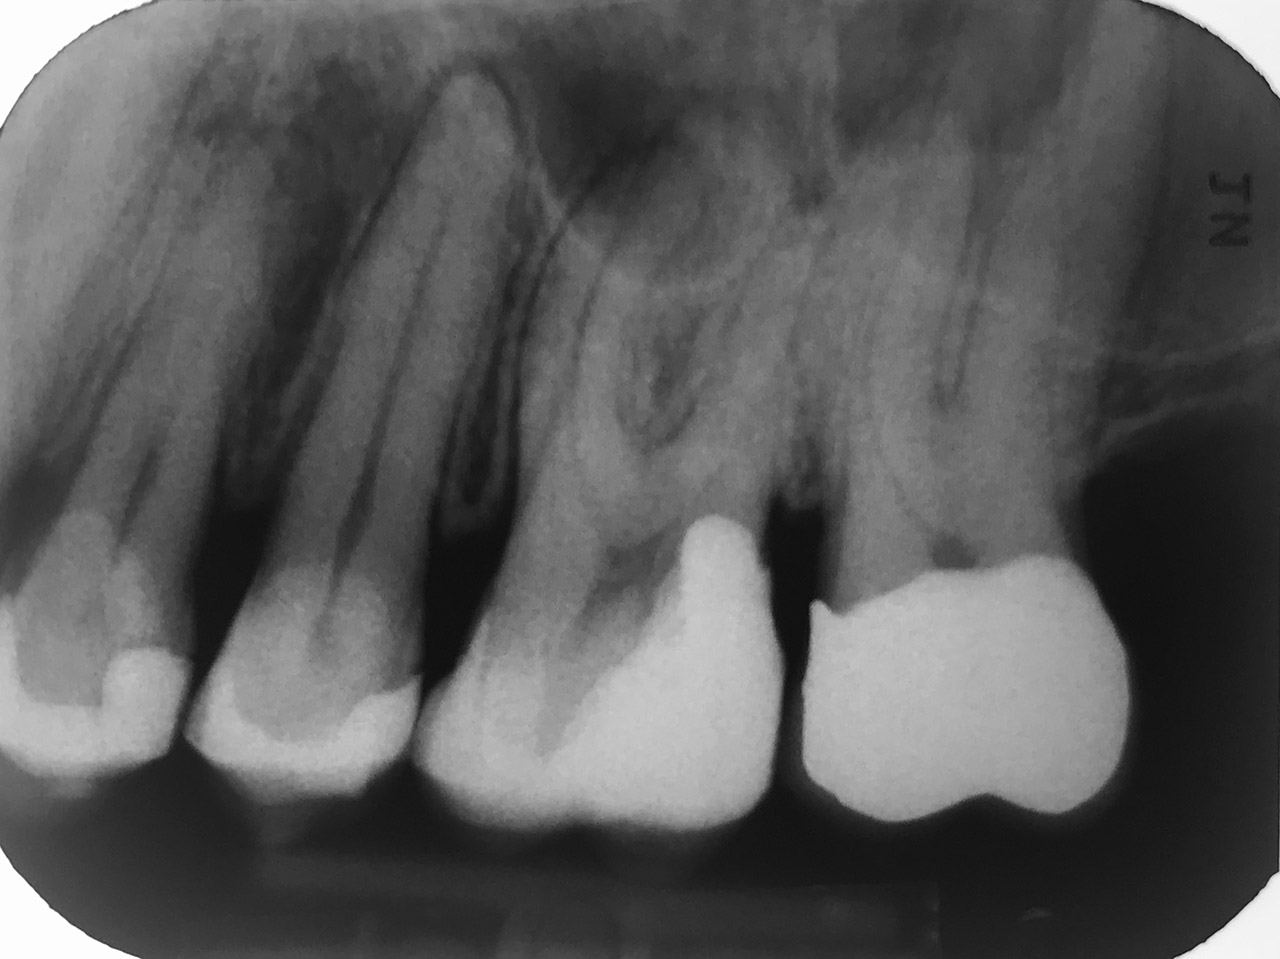

Endodontie/Wurzelbehandlung:

Befund: Aufbißschmerz und Schwellung auf Zahn 46. Frisch zementierte Krone (alio loco).

Therapie: Abnahme der Krone, Entfernung der Zementreste, Revision der insuffizienten Wurzelbehandlung.

Glasfaserstifte und neue Krone, beides adhäsiv zementiert.